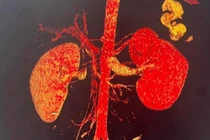

| Hàm răng giả được bác sĩ lấy ra từ thực quản bệnh nhân. Ảnh BVCC |